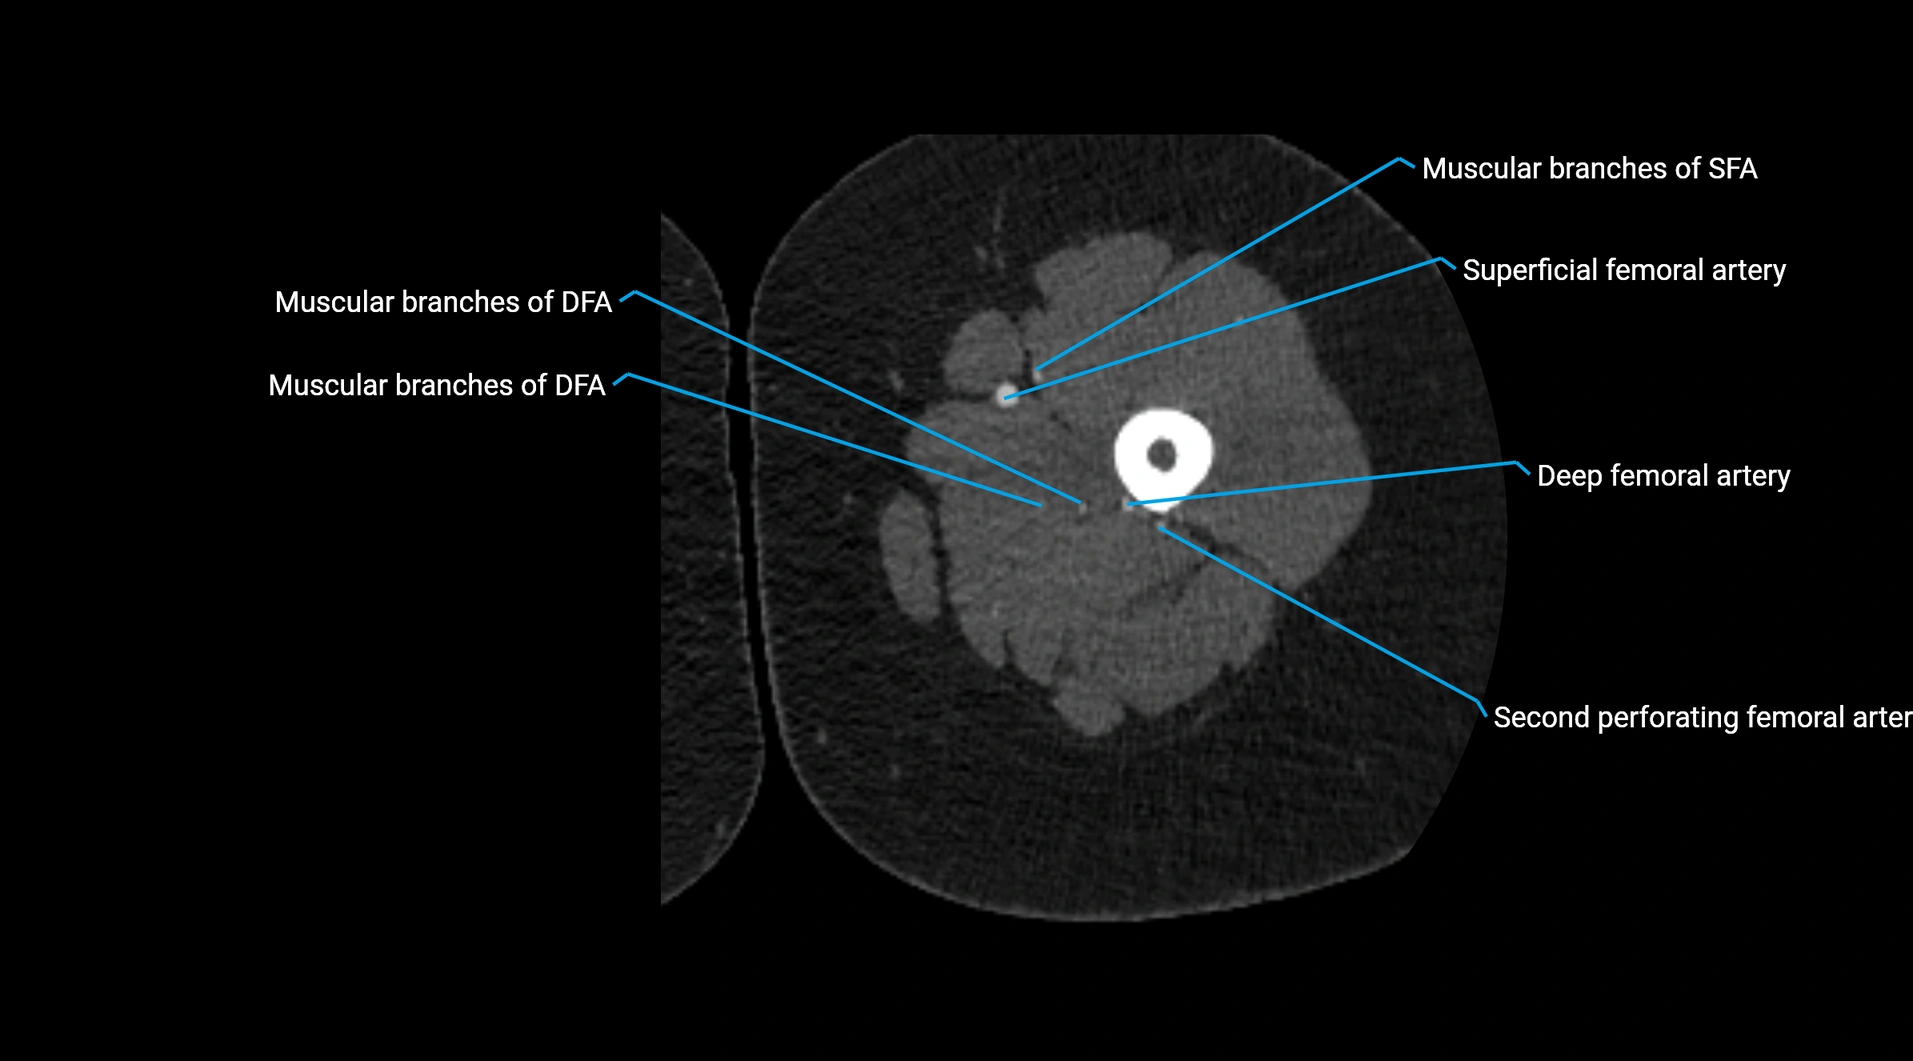

Contrast-enhanced CT (CTA):

• Gold standard for abdominal aortic imaging

• Provides excellent detail of lumen, wall, aneurysm, thrombus, and branch vessels

• Multiplanar and 3D reconstructions help in aneurysm measurement, stent graft planning, and dissection evaluation

• Detects acute rupture, traumatic injury, or occlusion with high sensitivity